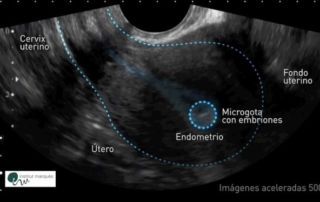

El útero se mueve para que los embriones se implanten correctamente

El equipo de Institut Marquès demuestra a partir de nuevas imágenes que, después de una transferencia embrionaria, el útero se mueve para mantener el embrión dentro de la cavidad uterina e impedir así que sea expulsado o implementado en un lugar inadecuado. El hallazgo se ha presentado este fin de semana en el Congreso Alpha [...]